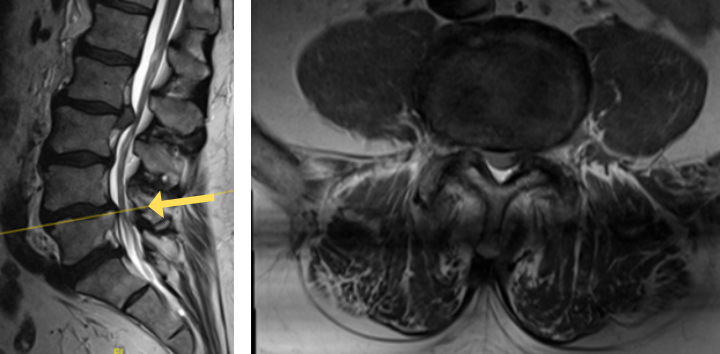

His MRI lumbar spine showed a herniated disc at L2/L3 and a grade 1 spondylolisthesis at L4/L5. Both of these findings were contributing to the patients back and leg pain.

Image 1B shows disc herniation at L2/L3.

The herniated disc only requires decompression and removal of the herniated disc. Notice in the same flexion extension dynamic x-rays. There’s no abnormal motion at the L2/L3 level.